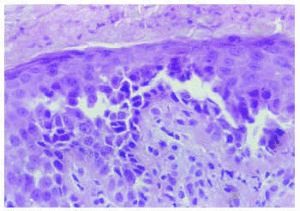

El hemograma y la bioquímica de rutina fueron normales. Se practicó una biopsia de una de las lesiones del cuello (figs. 3 y 4).

Fig. 4.--Detalle histológico a mayor aumento.

Histopatológicamente, en la epidermis se observaban hendiduras suprabasales que contenían queratinocitos acantolíticos. Algunas de las células mostraban disqueratosis, pero no se apreciaban cuerpos redondos. La superficie de la epidermis se mostraba hiperqueratósica, con orto y paraqueratosis. En la dermis existía un moderado infiltrado inflamatorio perivascular compuesto por linfocitos e histiocitos.

El estudio histopatológico se caracteriza por la existencia de acantolisis, edema intercelular, aspecto de «pared en ladrillos desmoronada» de la epidermis y en ocasiones presencia de células disqueratósicas, hecho que plantea el diagnóstico diferencial con la enfermedad de Darier. El estudio con inmunofluorescencia directa e indirecta es negativo, a diferencia de las enfermedades ampollosas autoinmunes. Con el microscopio electrónico se observa un defecto en la adhesión desmosómica, con separación de los tonofilamentos9.